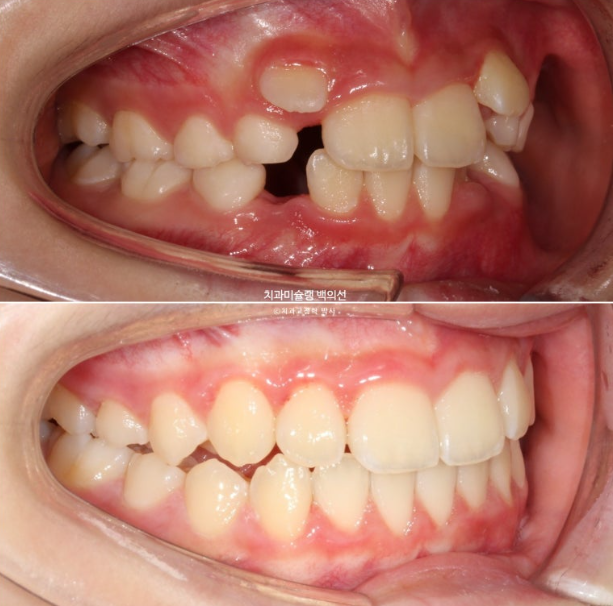

23.06~25.06

남아있는 유치는 없고 완전한 영구치열에 접어들었습니다.

나중에 2차교정을 안해도 될 정도가 되었습니다.

좋은 결과를 오래 유지하기 위해서 철사 고정식 유지장치 및 가철식 유지장치까지 꼼꼼하게 들어갑니다.

총 치료기간은 2년이고 중간에 쉬는 기간은 5개월이었습니다.